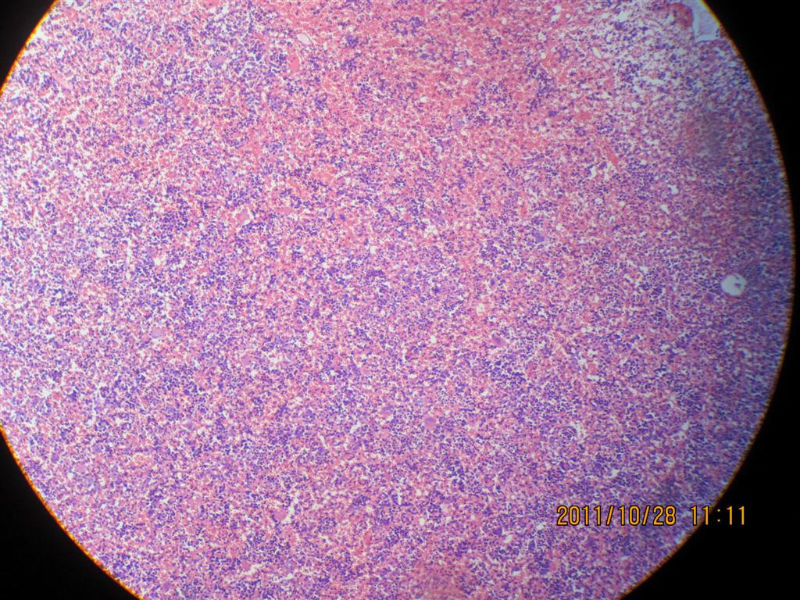

髓脂肪瘤